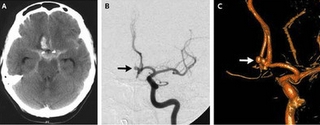

世界神经外科医师联盟(WFNS)委员会的蛛网膜下腔出血分级

WFNS分级 GCS评分 运动障碍 Ⅰ 15 无 Ⅱ 14 - 13 无 Ⅲ 14 - 13 有 Ⅳ 12 - 7 有或无 Ⅴ 6 - 3 有或无